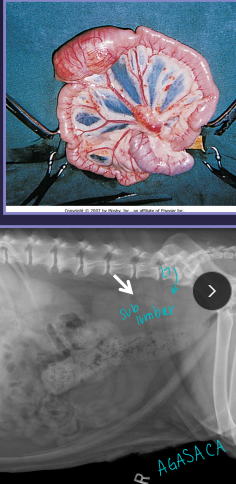

Splenic Torsion “acute abdomen”

Et: spleen twists on pedicle, congestion, necrosis

splenic artery and vein

Sig: Lg-breed dogs

Cs: shock(acute), anorexia, V/D, pain, enlarged spleen, hemoglobinuria(chronic), VPCs

Dt:

Rads: abnormal location, mass effect, gas bubbles, comma-shaped spleen

US: variable echotexture, dilated vessels, thrombi

Tx: splenectomy DO NOT untwist, Unasyn

necrotic debris → emboli risk